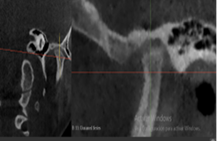

A través de los cortes tomográficos (Figura 3) se pudo observar que la rama mandibular derecha medía 43.85 mm y la izquierda 39.53 mm dando una diferencia de 4.34 mm lo que evidencia que la asimetría que presenta la paciente es a causa de la discrepancia de tamaño de las ramas mandibulares (A).

En el corte a nivel de la articulación temporomandibular izquierda se observó un aplanamiento del cóndilo con áreas de cambios osteoartríticos leves (B); en la articulación temporomandibular derecha el cóndilo se encuentra con una severa osteoartritis que muestra una imagen hipodensa a nivel condilar compatible con un quiste subcondral (C).

Diagnóstico de ATM: La paciente presenta una displasia discal sin reducción bilateral.

Plan de tratamiento: Debido a todo lo expuesto se decidió colocar un aparato de avance mandibular tipo monoblock para recapturar el disco. Para ello se inició con la realización de una mordida constructiva para la confección del aparato, se llevó a una coincidencia de las líneas media y un adelantamiento mandibular de 3 mm (Figuras D, E y F). Posteriormente se envió los registros para la confección del dispositivo de avance mandibular tipo monoblock (Klammt Clase II) que fue instalado en marzo del 2023 constatando de que se encuentre totalmente adaptado (G), las indicaciones de uso fueron más de 20 horas al día aconsejando que la paciente se lo retire únicamente para comer y para el aseo respectivo. Los controles se realizaron a las 2 semanas y después con una frecuencia mensual durante 12 meses.